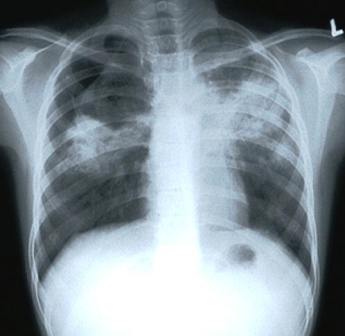

chest X-ray showing shadows caused by TB

Your doctor will order X-ray examination of your lungs if TB is suspected.

Damaged areas show up as shadows.